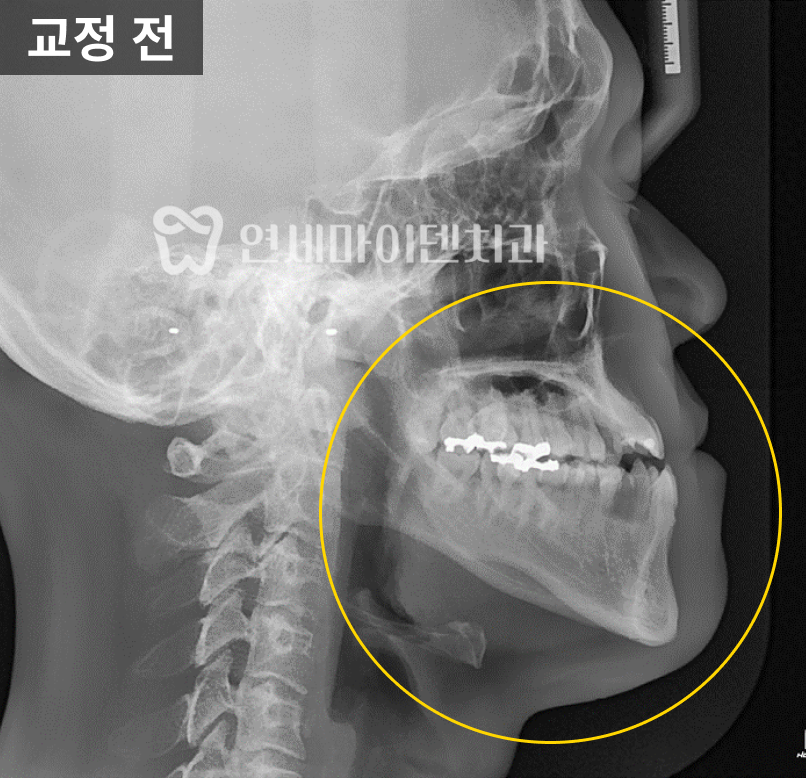

환자분의 편측 방사선 촬영본을 분석한 결과,

아래턱이 위턱에 비해 너무 길고 앞으로 돌출된 상태였습니다.

추가로 교정 정밀진단을 통해 수치를 분석했는데,

ANB 수치와 Wits 수치가 정상에서 많이 벗어난 상태였습니다.

ANB수치란 위턱과 아래턱의 가장 튀어나온 점 사이의 각도를 말하며,

정상은 2도~3도지만, 환자분은 –3도로 정상수치를 벗어났습니다.

Wits 수치란 교합평면의 기준으로 골격을 판단하는 수치로

정상은 -2도지만, 환자분은 -14.8도로 정상수치를 크게 벗어났습니다.

교정 정밀진단을 바탕으로 3급 부정교합 진단을 내렸습니다.